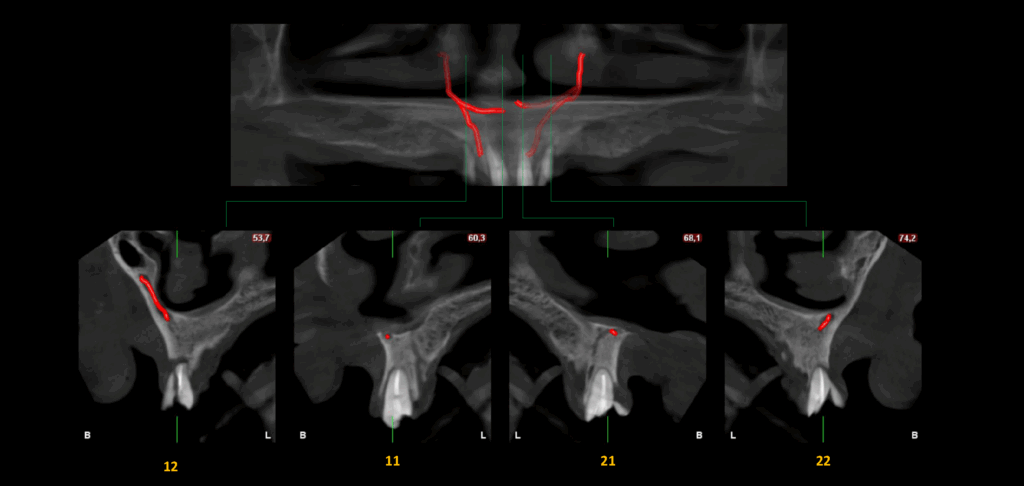

CORTES TRANSAXIALES

En el estudio complementario mediante tomografía computarizada de haz cónico (TCHC), se identifica la presencia del canalis sinuosus en el maxilar derecho, con trayecto que se dirige hacia la región ósea palatina correspondiente a las piezas 12 y 11. Asimismo, se evidencia un canalis sinuosus en el maxilar izquierdo, que se origina en la pared lateral de la fosa nasal izquierda y se dirige hacia la región ósea palatina y apical de las piezas 21 y 22.

Adicionalmente, se observa fractura radicular en la pieza 12, asociada a una imagen osteolítica periapical. Se identifican también fracturas radiculares con desplazamiento en las piezas 21 y 22. En la región correspondiente a la pieza 23, se evidencia un fragmento dentario sobre la cortical ósea vestibular.